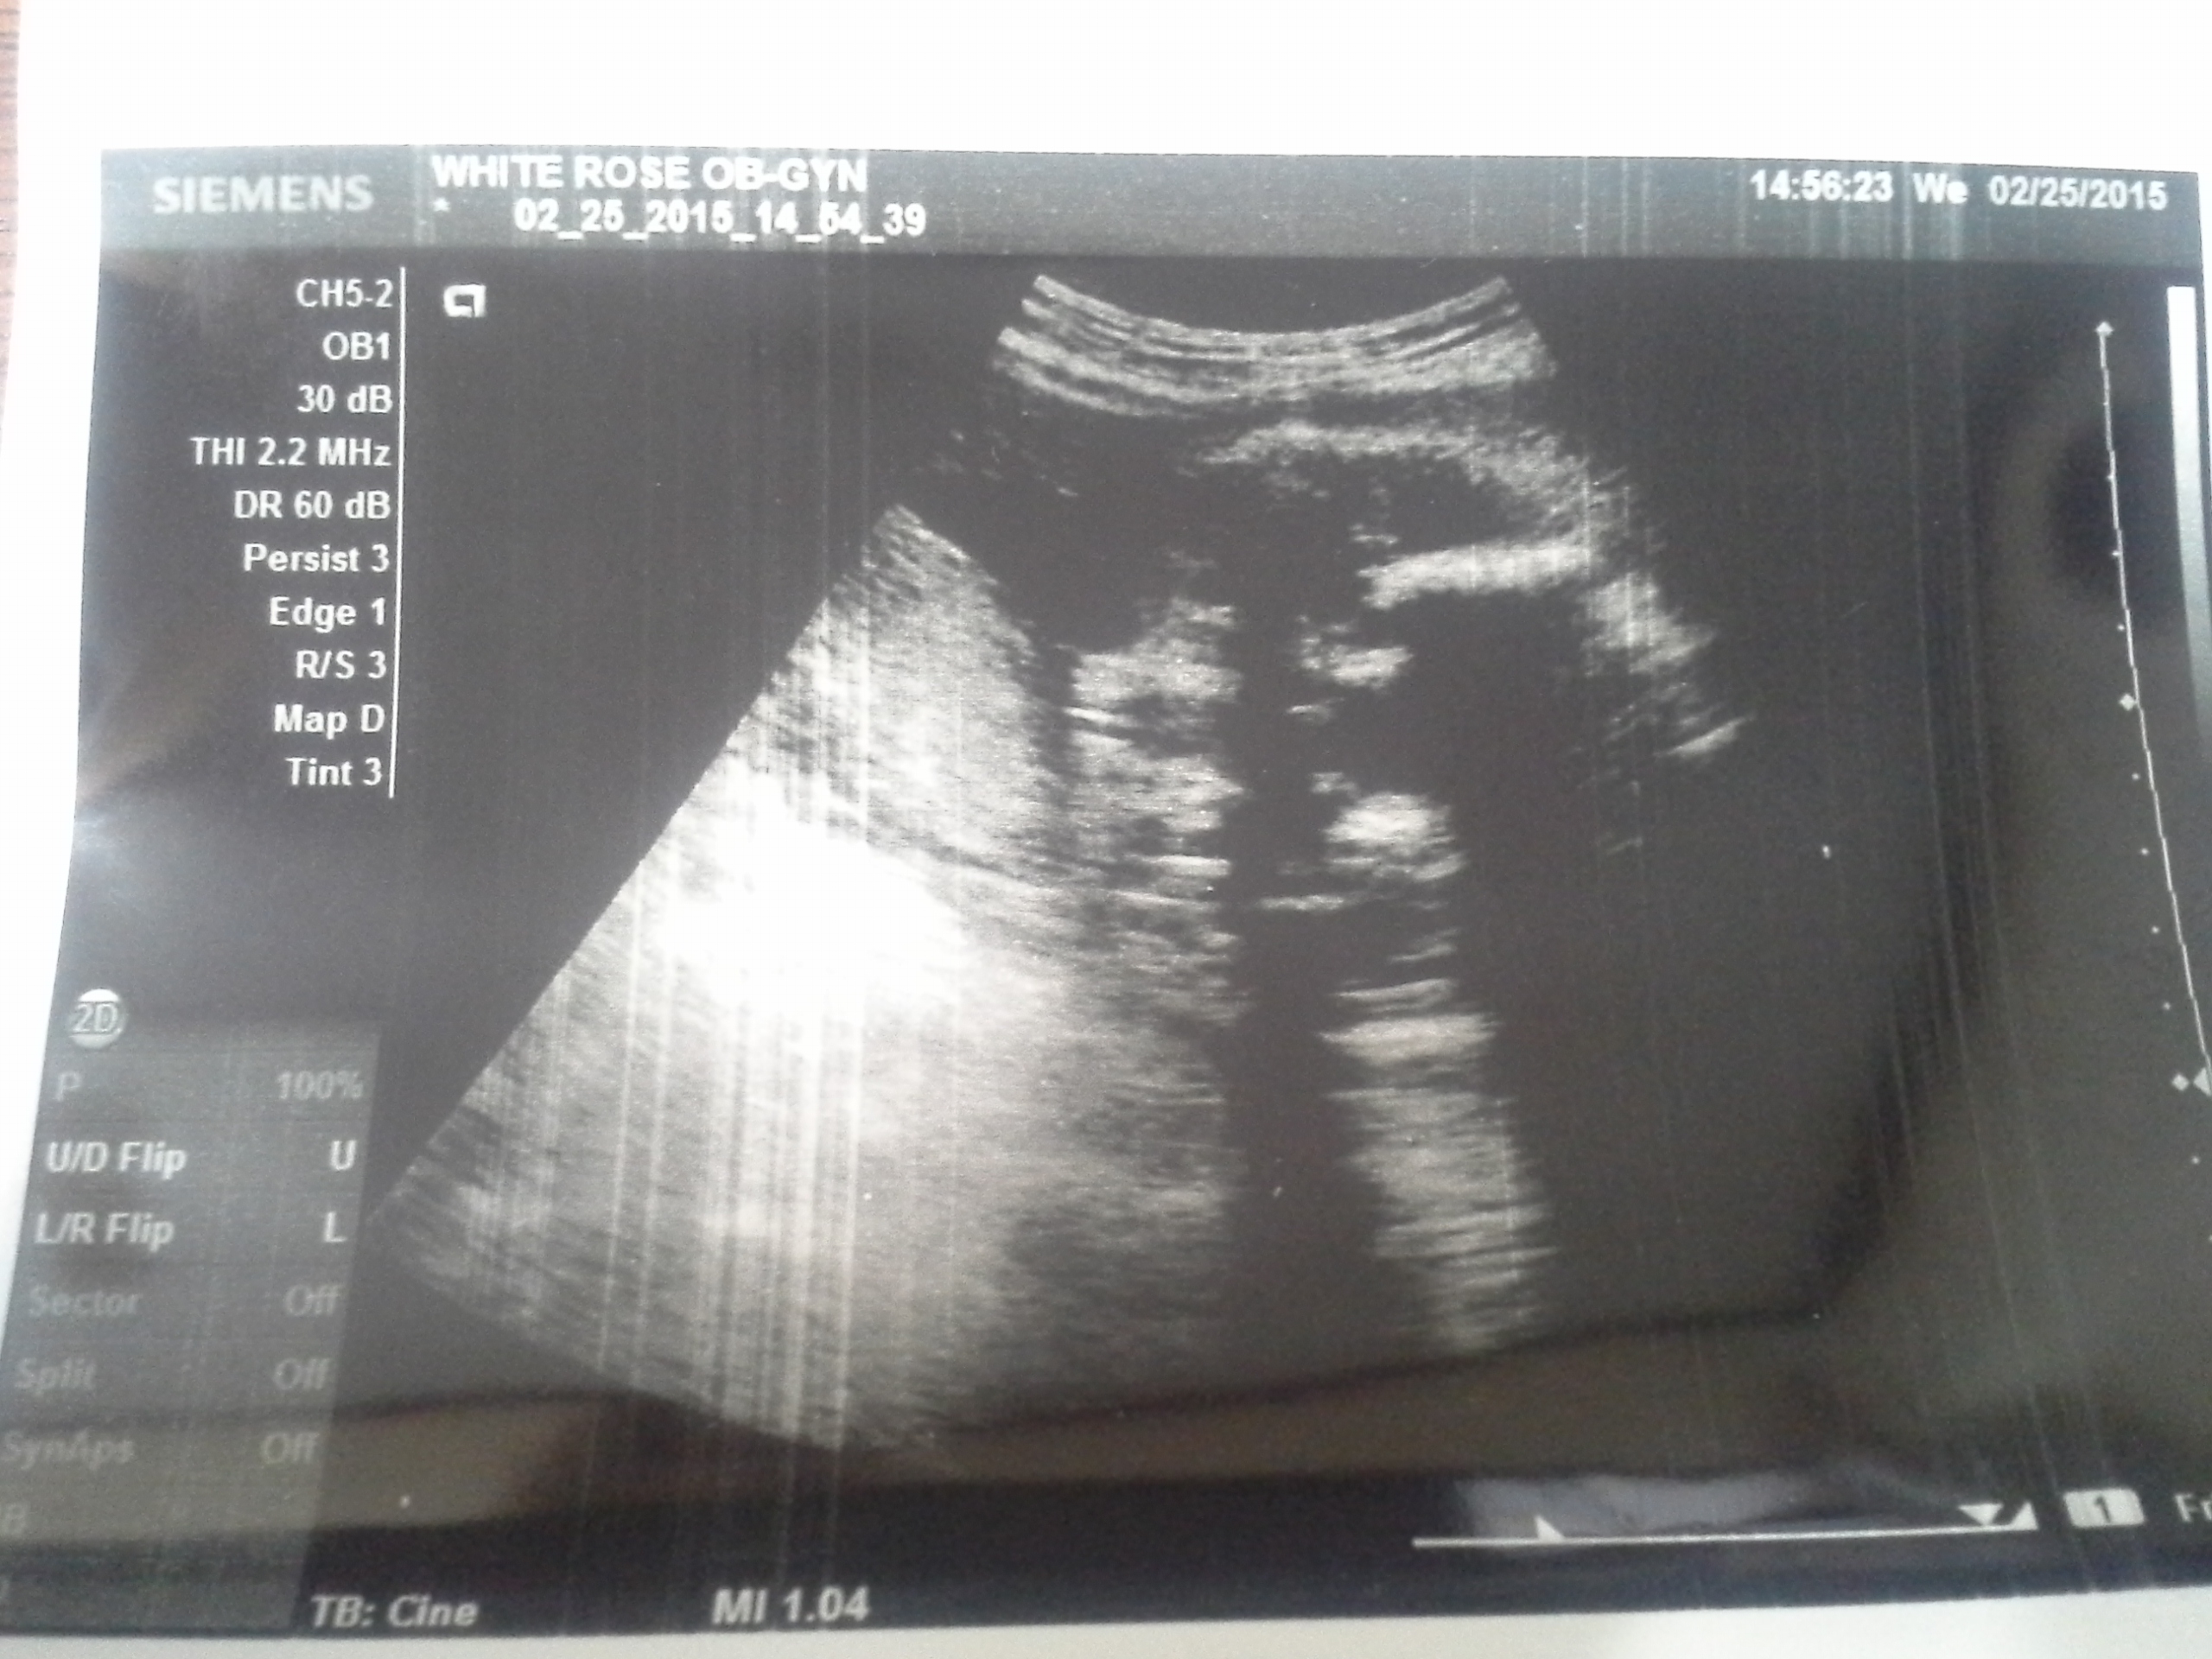

I would say girl :) Good Luck !!

Not the greatest image quality but looks girly!